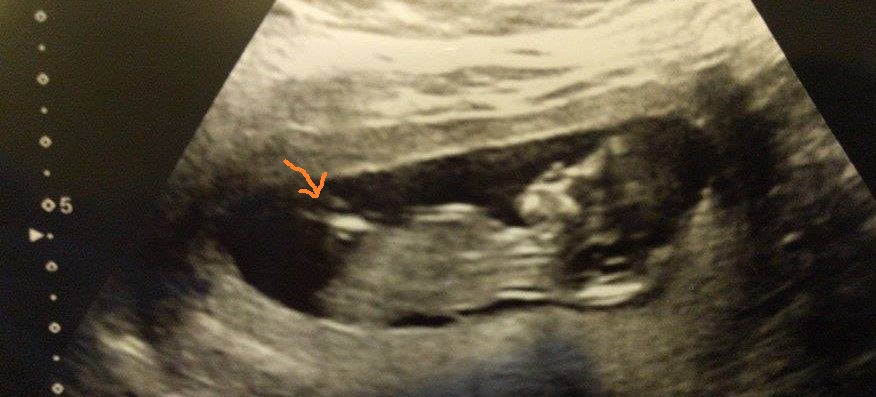

These scan photo's are just shy of 13 weeks! Baby girl or boy? :)

Thankyou for all your guesses so far! That's been my gut feeling since I had my bfp, although I won't be finding out untill the birth! Just incase I'm looking in the wrong place, is this the nub? (Im not too good at this!)Attachment 34701

This is the nub. There is a little bump on top which could mean boy. The bump could also be unrelated to the nub, so this is a tricky one.